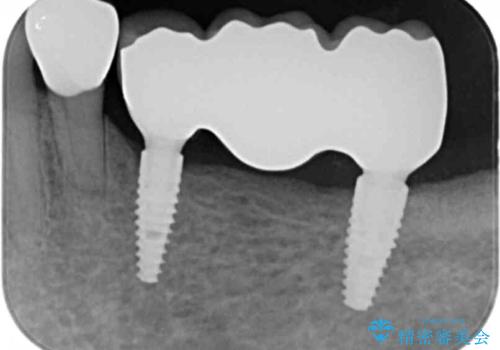

審美的・機能的に良好な位置に埋入するには、骨量が十分ではなかったため骨の造成を併用したインプラント埋入外科手術を行います。

前歯のインプラントを審美的に仕上げるには、インプラント周囲に十分な骨の量と厚みのある歯肉、そして埋入位置の精密な位置付けが重要です。